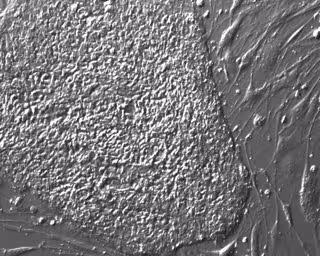

Células madre pluripotentes humanas diseñadas.

Células madre pluripotentes humanas diseñadas. - ALPHAMED PRESS